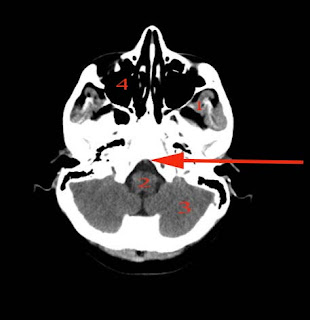

Brain IQ test

CT